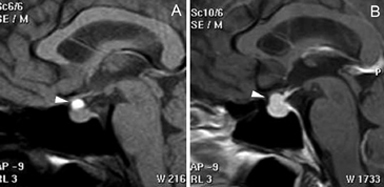

Figura 19A y B. Cortes sagitales T1w antes y después de inyección de Gadolinio. El tumor (prolactinoma) crece hacia caudal, invade el seno esfenoidal y erosiona el clivus (puntas de flecha), dejando libre la cisterna quiasmática. Los adenomas pituitarios invasores tienen características histológicas benignas, los malignos (carcinomas pituitarios) constituyen sólo el 0,2-0,5% de todos los tumores pituitarios50 y generalmente son macroadenomas funcionantes recidivados,que se presentan con metástasis subaracnoideas, cerebrales o sistémicas (Figuras 20 A, 20B, 20C y 20D).

Figura 20A y B. Cortes sagitales, secuencia T1 sin y con Gad. Prolactinoma maligno que invade el seno esfenoidal, el clivus, se extiende a la cisterna supraselar. C y D cortes axiales transversal y coronal, secuencia T1w con Gad. demuestran invasión subaracnoidea y del lóbulo temporal izquierdo (punta de flecha).